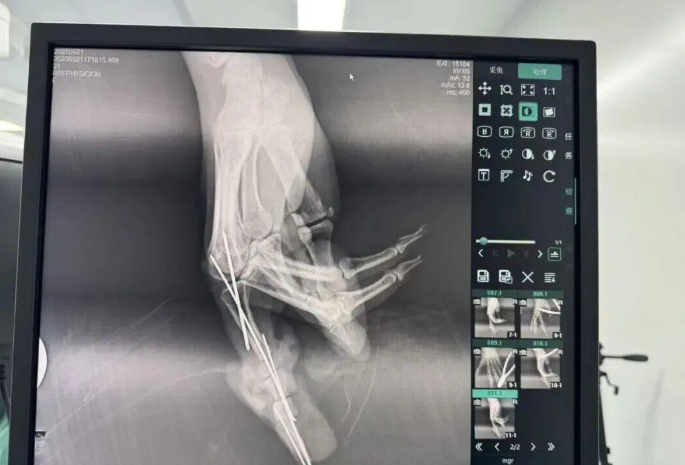

為確保手術(shù)成功,楊志主任特別聯(lián)合劉金海主任組成多手術(shù)組協(xié)作團(tuán)隊(duì),充分發(fā)揮梯隊(duì)配合優(yōu)勢,反復(fù)研討后確定了“組合式”手指再造方案:利用右足踇趾的皮瓣、末節(jié)甲床及部分趾骨,聯(lián)合第二趾的趾間關(guān)節(jié),再取部分髂骨進(jìn)行精確植骨,將這些組織精密拼裝,重建一個(gè)兼具良好外形和功能的新示指。

手術(shù)當(dāng)天,多手術(shù)組梯隊(duì)配合的優(yōu)勢得到充分體現(xiàn)。無影燈下,楊志主任與團(tuán)隊(duì)各司其職、緊密配合,一場漫長的生命接力就此展開。在放大40倍的專業(yè)手術(shù)顯微鏡下,醫(yī)生們開始了精細(xì)操作。楊志主任在術(shù)后解釋道:“患者需要吻合的血管直徑僅0.5-1.0毫米左右,末節(jié)手指的毛細(xì)血管更是細(xì)如發(fā)絲。我們必須將移植組織與手部的血管、神經(jīng)、肌腱進(jìn)行精準(zhǔn)吻合,確保移植組織通血成活。這不僅要求醫(yī)生有扎實(shí)的顯微外科技術(shù),還要具備專業(yè)的整形外科審美能力,才能讓再造的指尖既好用又好看?!?/p>

手術(shù)中團(tuán)隊(duì)發(fā)現(xiàn),由于葉女士患有多年的內(nèi)分泌系統(tǒng)疾病,其血管質(zhì)量不佳,存在血管內(nèi)膜分層、動脈頑固性痙攣等挑戰(zhàn)。面對這一情況,團(tuán)隊(duì)及時(shí)啟動應(yīng)急預(yù)案。“每一根血管的吻合都不能有絲毫偏差,稍有不慎就可能出現(xiàn)血管內(nèi)血流不暢,從而導(dǎo)致移植組織壞死?!睏钪局魅窝a(bǔ)充道。